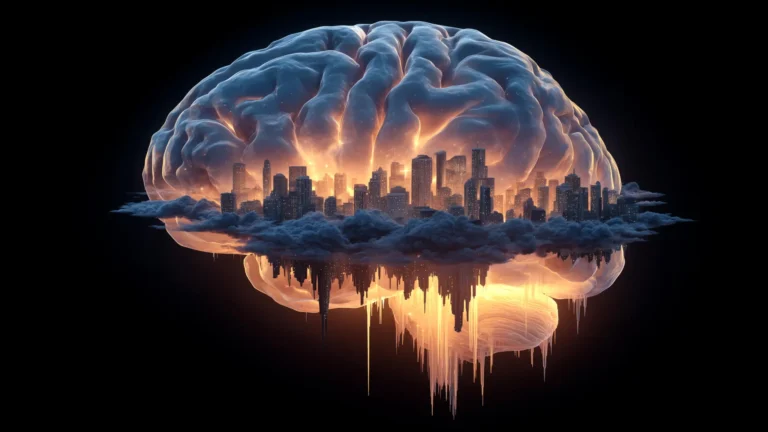

The pivotal contribution of the current study lies in its detailed exploration of how tanycytes actively participate in the elimination of detrimental molecules, such as misfolded tau proteins, thereby contributing to the overall health of the brain. The research meticulously demonstrated that these specialized cells possess a remarkable capacity to transport toxic substances, including aggregated tau, from the CSF into the systemic circulation. Once in the bloodstream, these waste products can then be efficiently processed and cleared from the body by peripheral organs. The study’s critical insight is that when this sophisticated transport mechanism mediated by tanycytes malfunctions or becomes compromised, the accumulation of toxic tau within the brain is an inevitable consequence.

The potential therapeutic ramifications of these findings are far-reaching and offer a new avenue for developing interventions aimed at combating Alzheimer’s disease. The researchers propose that strategies designed to preserve or restore the brain’s internal balance, by ensuring optimal tanycyte function, could prove instrumental in slowing the relentless progression of neurodegeneration. This perspective suggests that maintaining the integrity of the blood-brain barrier interface, where tanycytes reside, is not merely about passive protection but about active waste management.